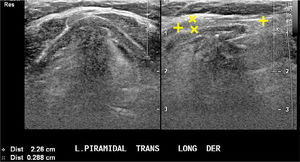

En el lecho tiroideo normal se identificará tejido hiperecogénico que corresponde a grasa; a la derecha entre la tráquea y la carótida común y a la izquierda entre la tráquea y la carótida común con mayor o menor presencia desde dorsal del esófago. Muchas veces vemos nódulos pequeños, hiperecogénicos, con sombra acústica, para y prelaríngeos, generalmente avasculares, que corresponden a granulomas calcificados en relación a material de sutura (Figura 10). En ocasiones estos granulomas alcanzan un mayor número y tamaño, pero generalmente hipo o avasculares.

Lecho post operatorio.

Cortes transversal cervical paratraqueal derecho, a dos niveles diferentes en el mismo paciente tiroidectomizado. No hay imagen de tejido tiroideo. Dos pequeñas estructuras hiperecogénicas, con sombra acústica posterior, con caracteres de nódulo calcificado, adyacentes a la tráquea.